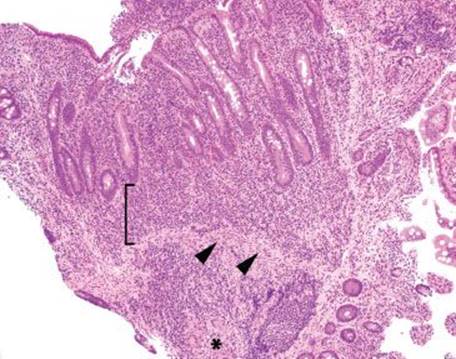

Figure 3.51 Acute ileitis pattern. Acute ileitis refers to acute inflammation in the epithelium of the ileum (arrowheads). It is most commonly caused by medication, infection, and inflammatory bowel disease.

Similar to that in the acute duodenitis pattern, acute inflammation in the epithelium of the ileum can qualitatively be scored “mild,” “moderate,” or “marked” based on the relative prominence of acute inflammation in the epithelium (Figs. 3.51–3.55). Comparatively, the acute ileitis pattern is associated with a slightly modified differential diagnostic list of etiologic considerations. In this section, the discussion emphasizes etiologic considerations particularly important to the ileum.

Figure 3.52 Acute ileitis pattern, aphthoid lesion. The diagnosis of acute ileitis implies the absence of chronic injury, as seen in this figure). Although the lymphoid aggregate is gently pushing apart the crypts, there is no chronic injury of the epithelium (note the epithelium could be theoretically peeled off the lymphoid aggregate since the epithelium is not tethered to the lymphoid aggregate by destructive inflammatory injury).